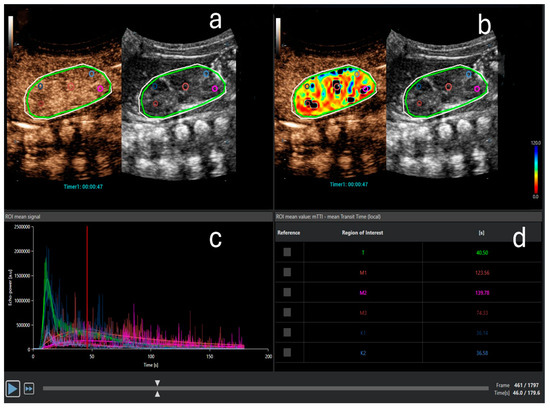

5. Contrast-Enhanced Ultrasound (CEUS) in AKI